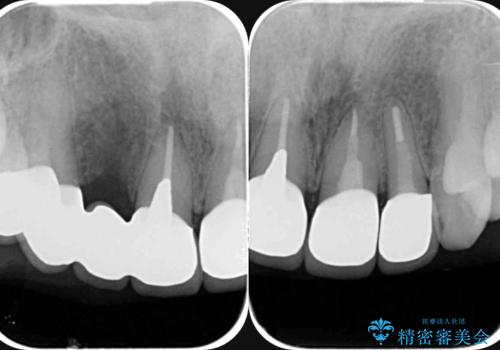

- 以前治療した前歯のセラミックの歯ぐきの位置がかわってしまい境目の変色の改善を希望して来院されました。

大きな穿孔が見られた、右上側切歯の抜去をこないブリッジの設計を含めた前歯の審美性の改善を目的とするセラミック治療を行いました。